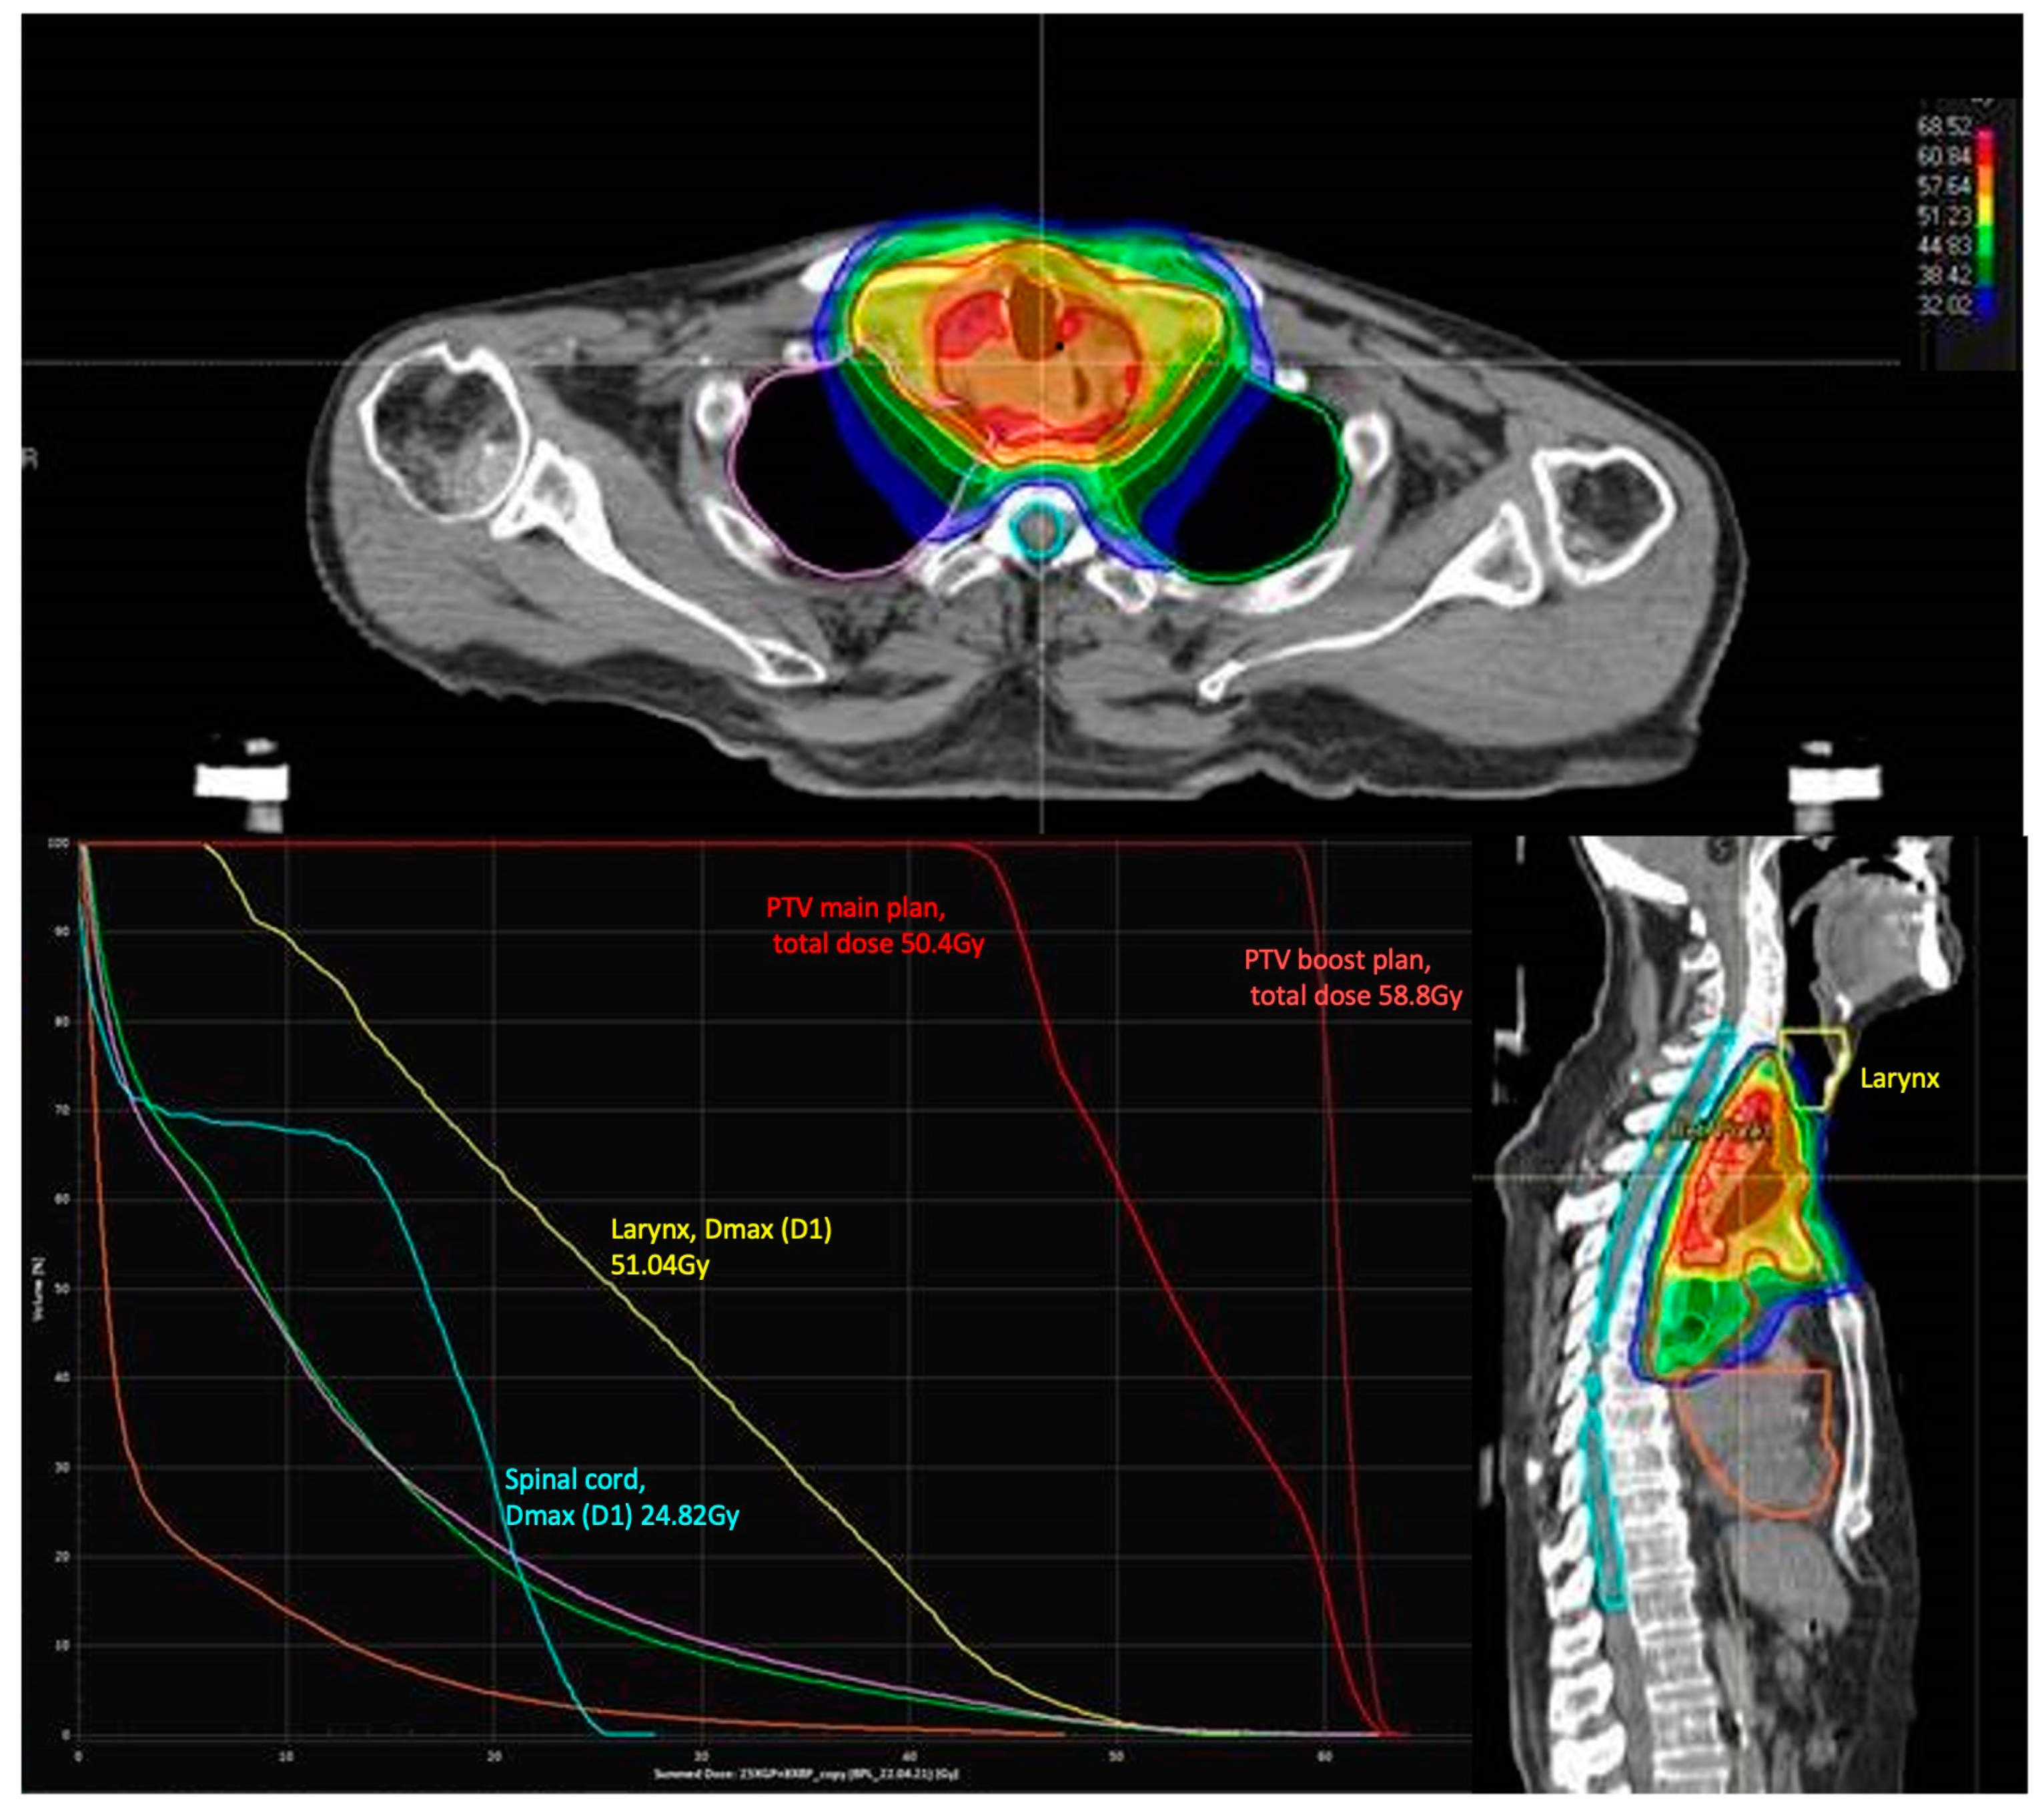

| Radiotherapy Treatment Characteristics | n (%) |

|---|---|

| RT technique | |

| 3D-CRT | 8 (14.5%) |

| IMRT | 47 (85.5%) |

| Mean total dose primary tumor and lymph nodes | 48.2 Gy (range:41.4–58.8 Gy) |

| Mean single dose primary tumor and lymph nodes | 1.8 Gy (range:1.8–3.0 Gy) |

| Mean total dose larynx | 40.0 Gy (range 14.3–68.0 Gy) |

| Irradiation cervical lymph nodes | |

| Yes | 55 (100.0%) |

| No | 0 (0%) |

| Mean PTV volume | 844.6 ccm (range 322–1322 ccm) |